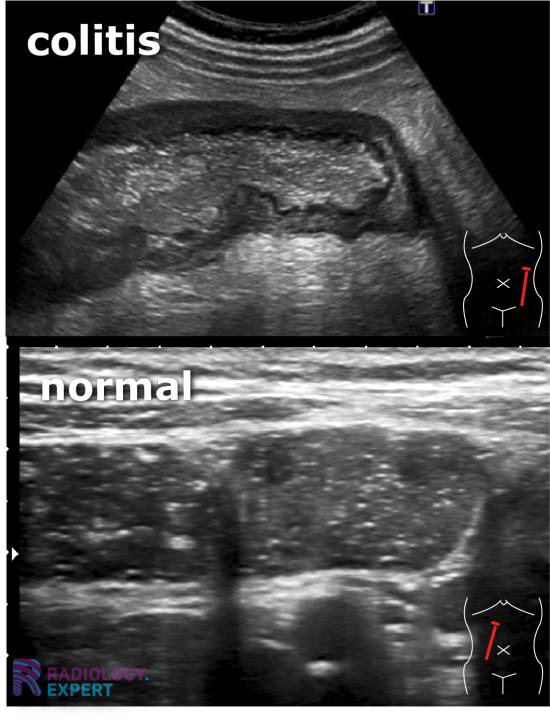

From www.radiology.expert